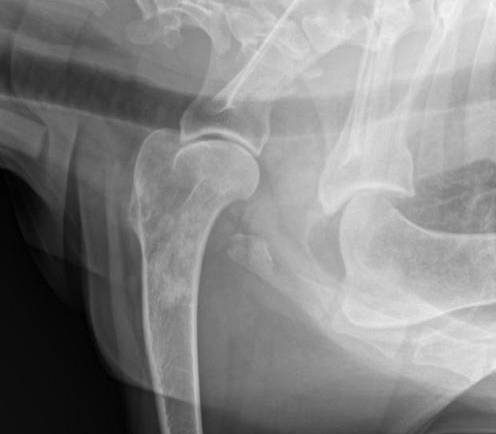

El osteosarcoma (OSA) apendicular es el tumor primario de hueso más común en la especie canina. Es un tumor mesenquimatoso maligno de células óseas primitivas, estas células producen una matriz extracelular de osteoide. Osteosarcoma. Representa hasta el 85% de las neoplasias que se originan en el esqueleto, la demografía ha sido bien informada, es en